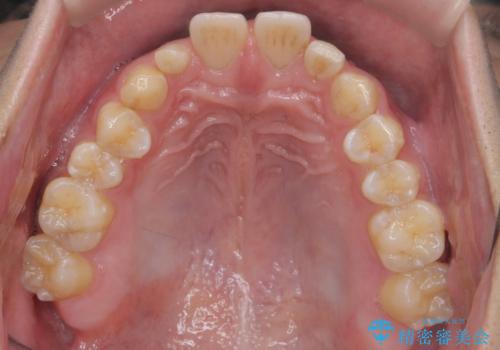

上下のかみこみがきつい場合で上にだけすき間がある場合は、上のすき間を閉じきるのは難しいことが多いです。

理由としては、すき間を閉じるには上の前歯は後ろに下がる形に動かないと無理なのですが、かみこみがきつい(かみ合わせがきつい、上下が深く咬んでいるともいいます)場合は、すぐ後ろに下の歯がかみこむためその動きができないためです。

さらに下の前歯にがたつきがある場合は下の前歯を後ろに下げること自体が難しくなるため、生まれつき歯の形が特殊な場合は、上のすき間を適切な位置にずらして、しかるべき歯にセラミッククラウンを被せて形態修正とスペースを埋めるというのが効率の良い治療方法と言えます。